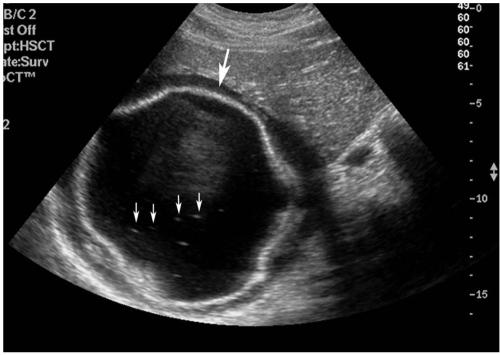

Hydatid disease (HD) is an endemic illness in many countries, and it poses an important public health problem that's influenced by peoples' socioeconomic status and migration that spreads this disease. Although rare, it may occur in any organ or tissue. The most common site is the liver (59-75%), followed in frequency by lung (27%), kidney (3%), bone (1-4%) and brain (1-2%). Other sites such as the heart, spleen, pancreas and muscles are very rarely affected. Unusual sites for this disease can cause diagnostic problems. This pictorial essay illustrates various radiological findings of HD in the liver, spleen, kidney, pancreas, peritoneal cavity, omentum, adrenal, ovary, lung, mediastinum and retroperitoneum. Familiarity with the imaging findings of HD may be helpful in making an accurate diagnosis and preventing potential complications.